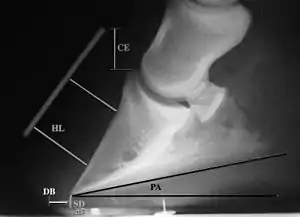

Radiographic measurements

Radiographic measurements, including coronary extensor distance (CE), horn:lamellar distance (HL), sole depth (SD), digital breakover (DB), and palmar angle (PA)

Several radiographic measurements, made on the lateral view, allow for objective evaluation of the episode.

1. Coronary extensor distance (CE): the vertical distance from the level of the proximal coronary band to the extensor process of P3. It is often used to compare progression of the disease over time, rather than as a stand-alone value. A rapidly increasing CE value can indicate distal displacement (sinking) of the coffin bone, while a more gradual increase in CE can occur with foot collapse. Normal values range from 0–30 mm, with most horses >12–15 mm.[1]

2. Sole depth (SD): the distance from the tip of P3 to the ground.

3. Digital breakover (DB): distance from the tip of P3 to the breakover of the hoof (dorsal toe).[1]

4. Palmar angle (PA): the angle between a line perpendicular to the ground, and a line at the angle of the palmar surface of P3.

5. Horn:lamellar distance (HL): the measurement from the most superficial aspect of the dorsal hoof wall to the face of P3. 2 distances are compared: a proximal measurement made just distal to the extensor process of P3, and a distal measurement made toward the tip of P3. These two values should be similar. In cases of rotation, the distal measurement will be higher than the proximal. In cases of distal displacement, both values will increase, but may remain equal. Therefore, it is ideal to have baseline radiographs for horses, especially for those at high-risk for laminitis, to compare to should laminitis ever be suspected. Normal HL values vary by breed and age:[1]

• Weanlings will have a greater proximal HL compared to distal HL

• Yearlings will have approximately equal proximal and distal HL

• Thoroughbreds are usually 17mm proximally, and 19mm distally

• Standardbreds have been shown to have a similar proximal and distal HL, around 16 mm at 2 years old, and 20 mm at 4 years old

• Warmbloods have similar proximal and distal values, up to 20 mm each

• HL tends to increase with age, up to 17 mm in most light breeds, or higher, especially in very old animals